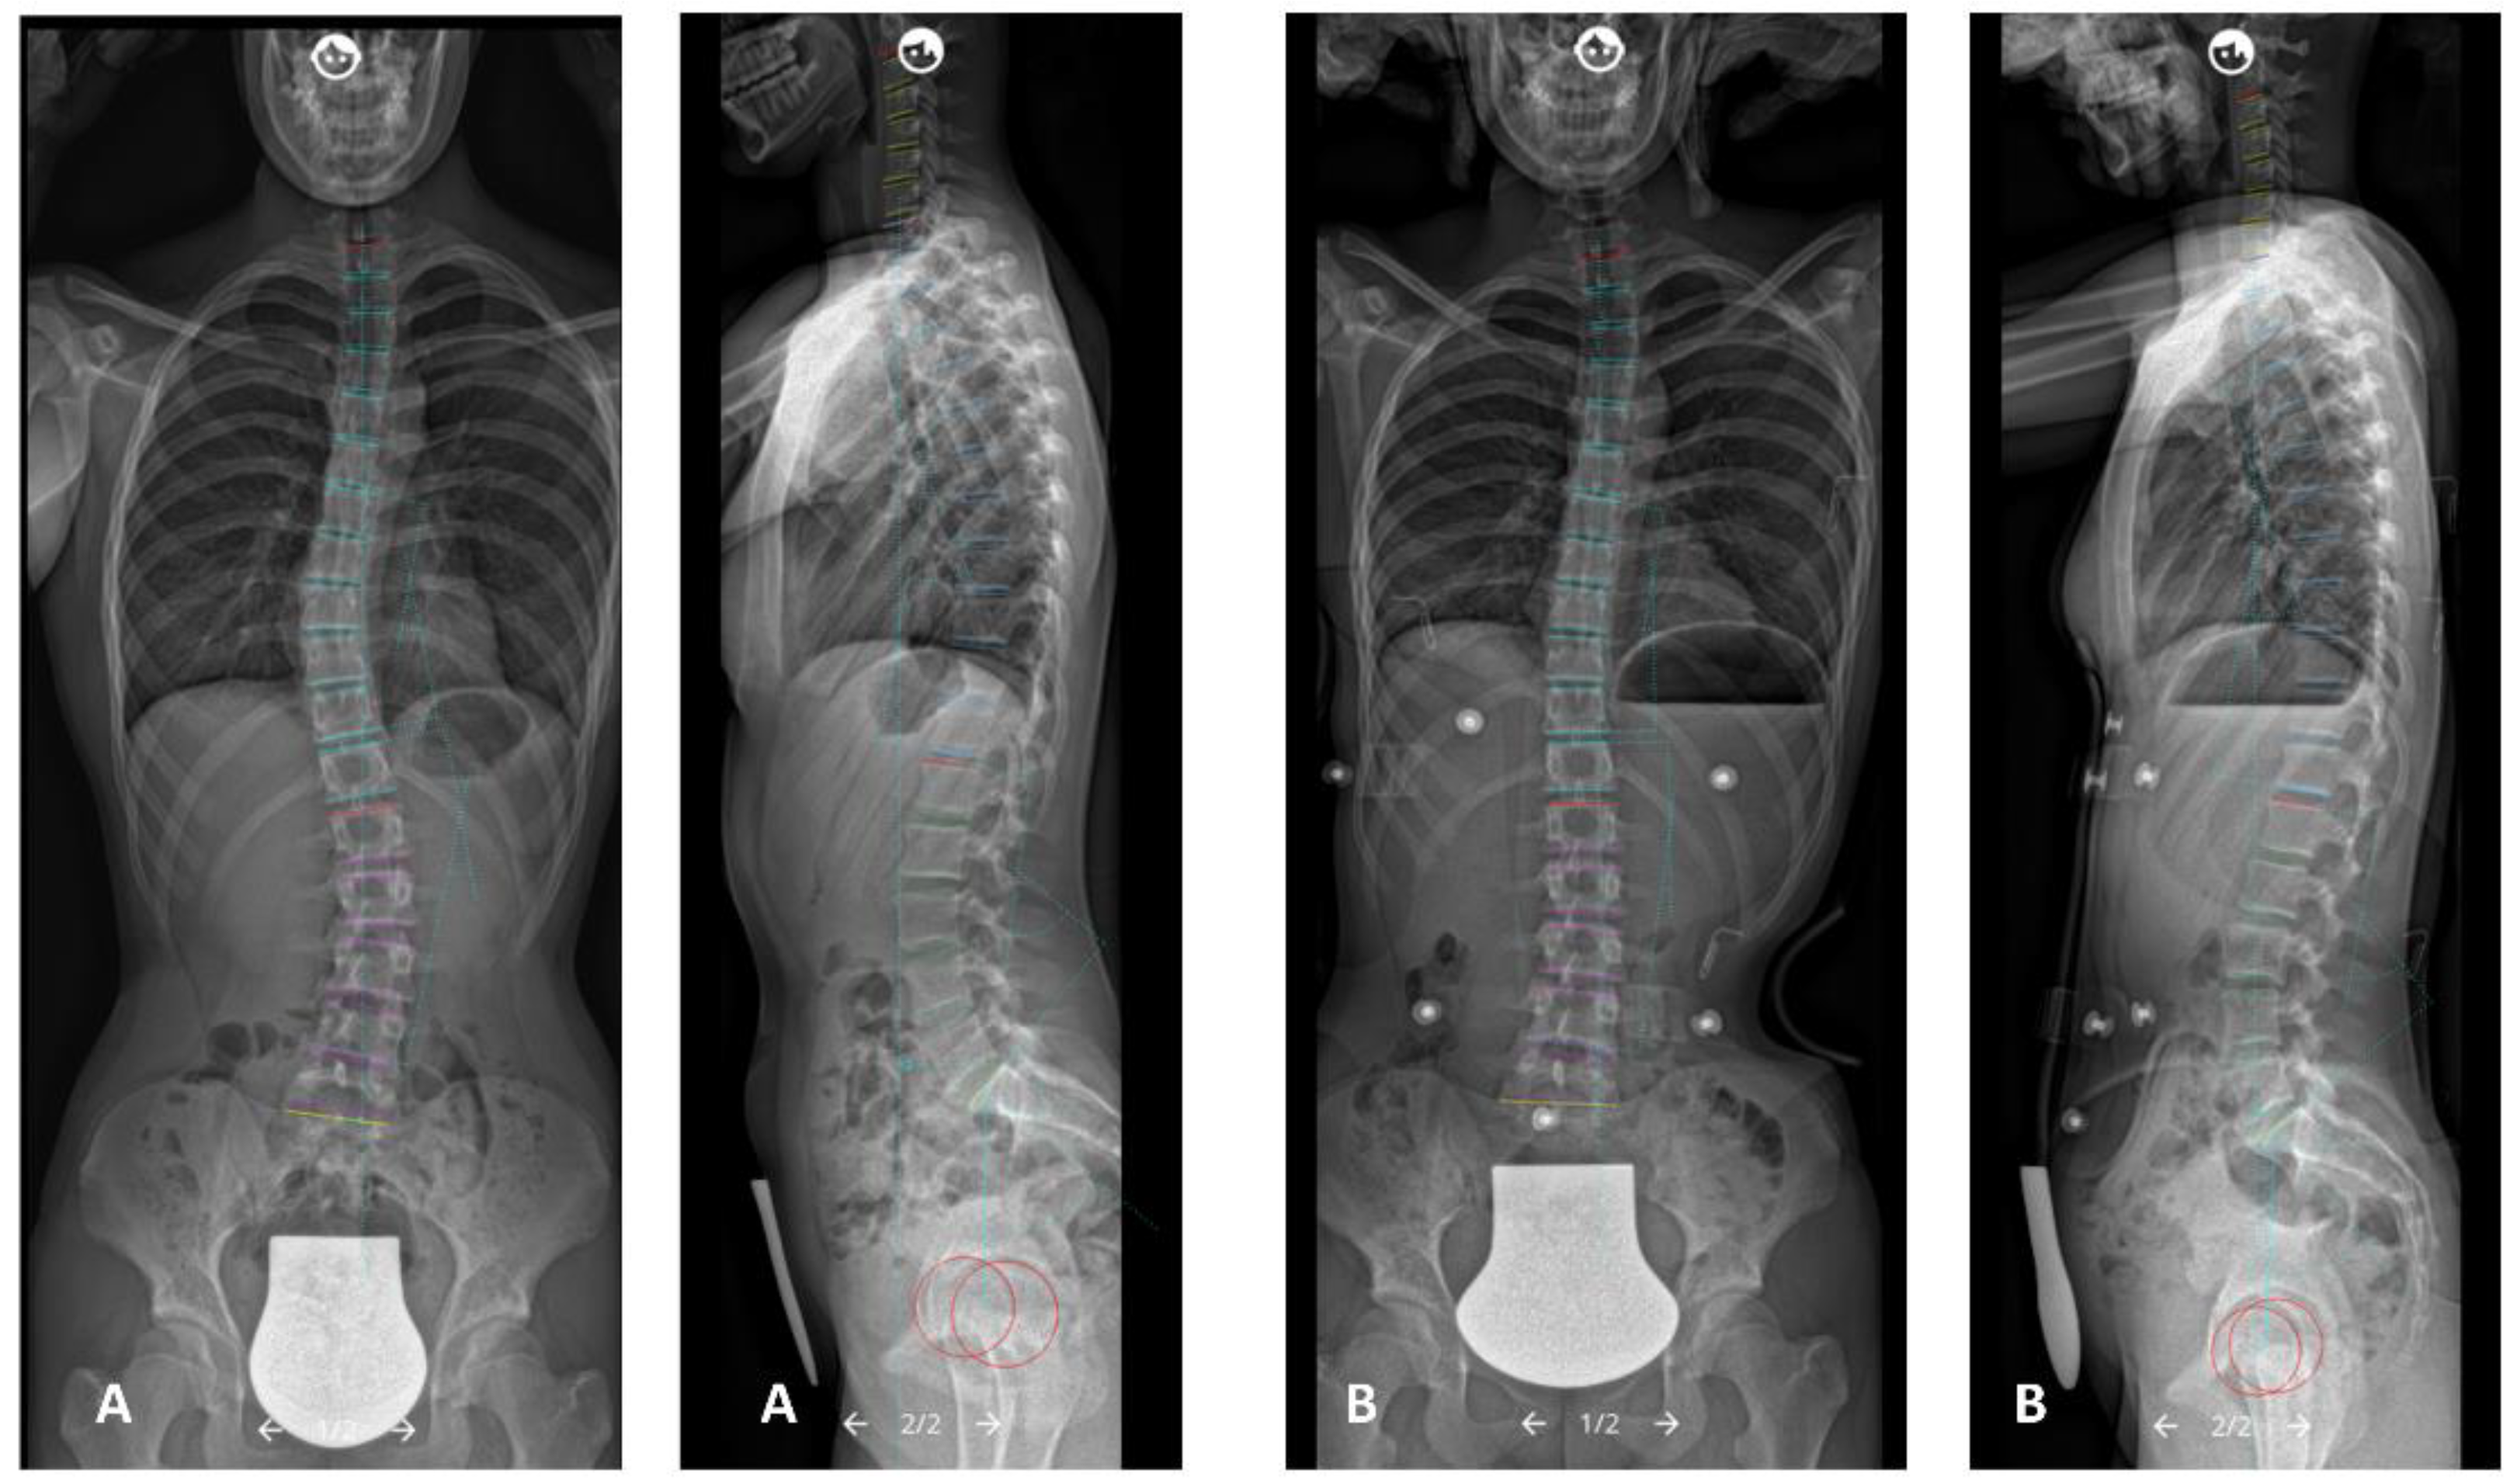

Full spine radiographs were acquired using a low-dose biplanar EOS-imaging device (EOS-imaging®, Paris, France) or conventional radiography. Radiographic controls were performed before the brace, in-brace, and at follow-up after finished brace therapy. First, in-brace radiographic controls were performed after completing the fabrication process of the C-brace. In all radiographic controls, all patients had their hands on their cheeks to avoid the upper extremities overlapping the spine [25], were barefoot, and were instructed to look straight ahead. Patients, whose radiographs that did not pass the mentioned requirements were not included. Data were stored as a digital imaging and communications in medicine file (DICOM). Analysis of the radiographic controls was conducted with Surgimap software (Surgimap®, New York, NY, USA) [26] (Figure 1). Radiographic measurements were performed by a single reader (W.M.), a research fellow and consultant for spine surgery. Radiographic parameters included the following:

Figure 1.

(A) Pre- and (B) in-brace anterio-posterior and lateral radiographs illustrating the analyzed spinal parameters (measurements with Surgimap software (Surgimap®, New York, NY, USA)).

Coronal parameters: primary Cobb angle for main curve, secondary Cobb angle for compensatory curve, coronal alignment (Calignment), C7-plumbline (C7PL).

Sagittal spinopelvic parameters: T1–T12 thoracic kyphosis TK (T1–T12), T4–T12 thoracic kyphosis TK (T4–T12), L1-S1 lumbar lordosis (LL), pelvic incidence (PI), pelvic tilt (PT), sacral slope (SS), C7-S1 sagittal vertical axis (SVA), T1-spinopelvic inclination (T1 SPi), T9-spinopelvic inclination (T9 SPi).

Axial plane parameters: apical vertebral rotation (AVR) of the primary curve (Raimondi 1). Raimondi rotation angle is an established method for the measurement of vertebral rotation in standard radiographs of the spine [27].